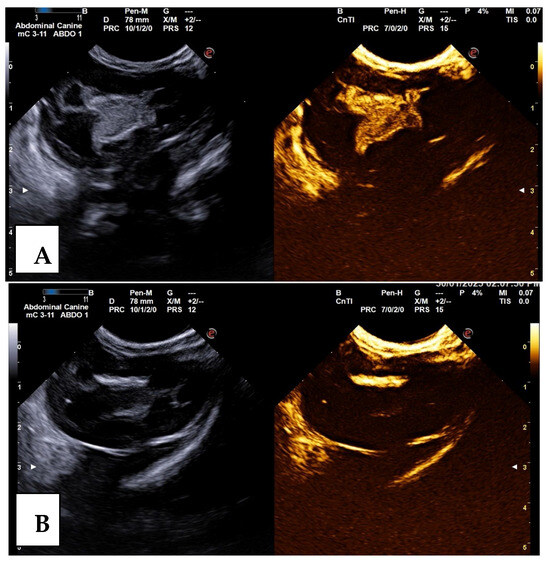

2.2.1. Contrast-Enhanced Voiding Ultrasonography (CE-VUS)

Post-Contrast US

2.3. VUR Assessment